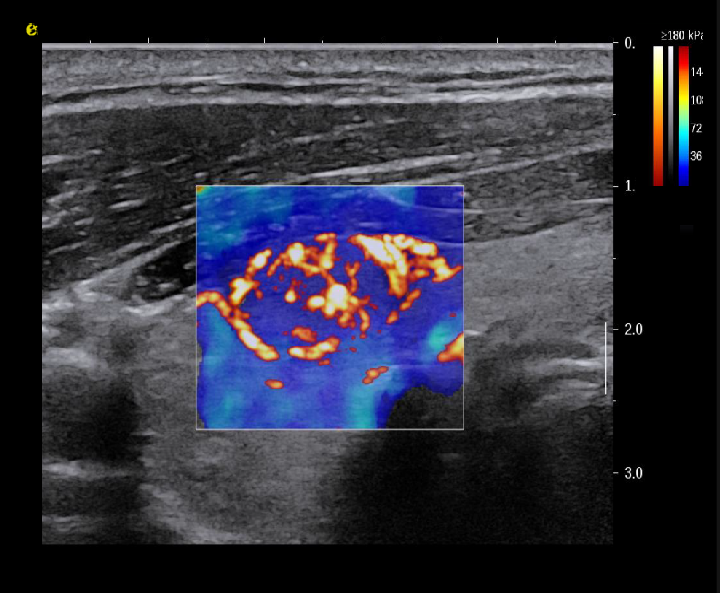

多模态复合成像

![]() 与传统单一成像模式相比,多模态复合成像技术能在同一幅图像中同时呈现二维组织信息、组织血管结构及其分布,以及组织硬度信息。这种成像方式使医生能够更直观地观察病变组织的解剖结构、血液供应和硬度状况,从而为临床治疗方案的制定提供更具体、形象的参考。

与传统单一成像模式相比,多模态复合成像技术能在同一幅图像中同时呈现二维组织信息、组织血管结构及其分布,以及组织硬度信息。这种成像方式使医生能够更直观地观察病变组织的解剖结构、血液供应和硬度状况,从而为临床治疗方案的制定提供更具体、形象的参考。